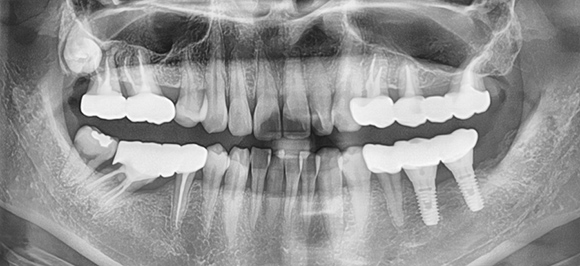

정확한 진단을 바탕으로 기능성과 심미성을 고려한 맞춤형

체계적인 시스템으로 철저한 관리 프로그램을 시행